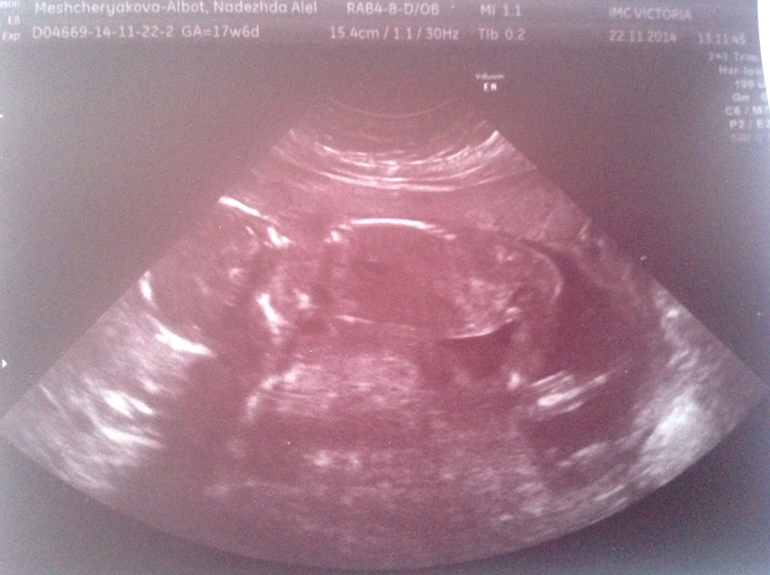

Вот и мы вчера прошли наш долгожданный скрининг, ходили с мужем в его день рождение платно к одному из лучшей врачей Иркутска, врач нам очень понравилась, всё подробно рассказала, показала!)) первые фразы: ребёночек лежит в низ головой, ой да это девочка у нас!)) так что ждем нашу долгожданную девчушку)))

Нам наконец-то рассчитали с учетом моего короткого цикла срок Б и ПДР. 18 неделек и 3 дня, и мы доросли на этот срок, на первом скрининге отставали на 5 дней. ПДР 22.04.2015. Весим мы уже 240гр, все косточки и органы в норме, всё хорошо функционирует))) наш папа был очень доволен)) малышка сначала спала, потом проснулась, но личико никак показывать не хотела, помахала нам ручкой и пинала ножками)) я бы вечно могла лежать и наблюдать за нашей крошкой, это так приятно)))